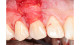

The images contained in this gallery are the property of Dr. Edward Gottesman.

Images have not been digitally altered in any way, shape, or form. These images may not be copied, downloaded or distributed without their express written permission.

Warning: Some surgical photos are intended for clinical and educational purposes and may be too graphic for some viewers.